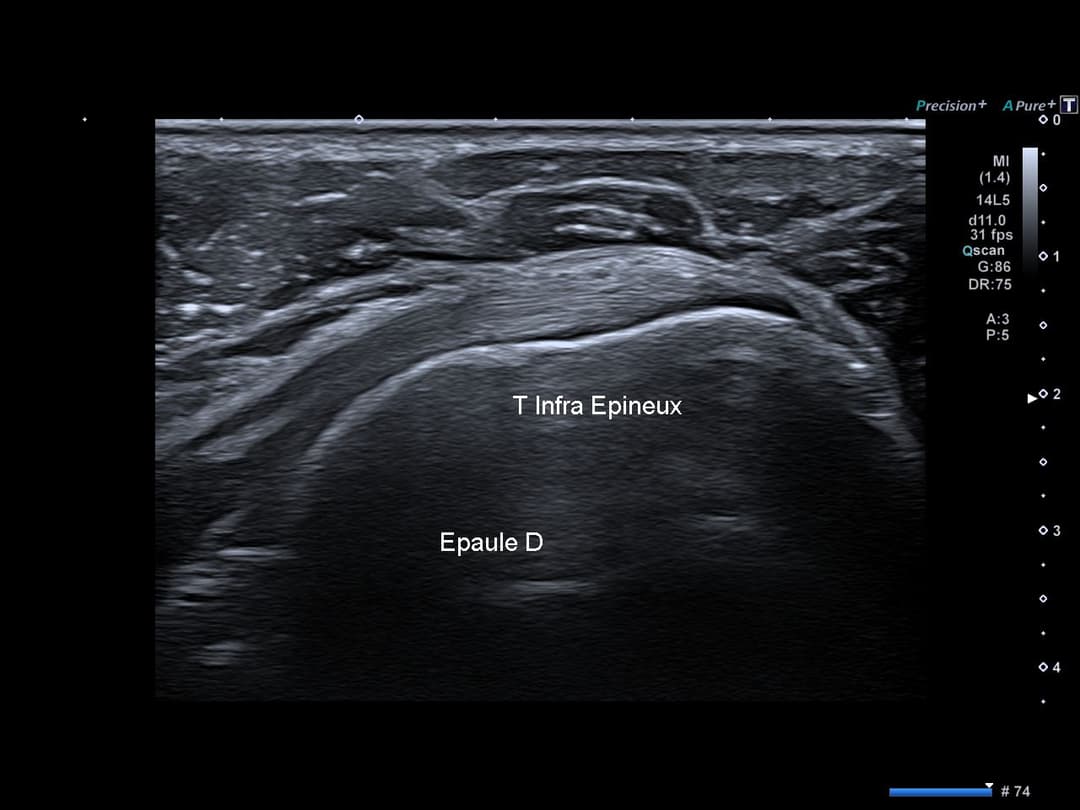

Tendon infra épineux normal